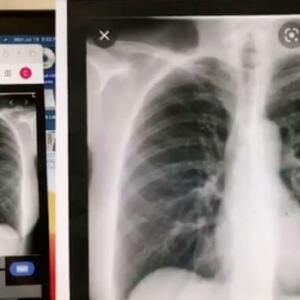

Šanel se dugo osećala neprijatno, a nakon nekog vremena počela je i da ima problema sa sistemom za varenje. Zbog toga je sprovela dalje testove. Kolonoskopija obavljena 2020. godine otkrila je nešto što mlada majka nije očekivala - veliki tumor u debelom crevu.

Ženi je dijagnostikovan maligni kolorektalni karcinom, koji je dostigao IV stadijum.

Lekari su odlučili da odmah uklone maligni tumor, ali se rak proširio dalje na jetru. Žena je morala da prođe kroz opsežnu hemoterapiju praćenu terapijom zračenjem. Borba protiv raka bila je veoma teška, a bolest se vraćala sa metastazama. Kada je rak napao jajnike, limfne čvorove, dijafragmu i pluća, Šanel je rečeno da ima najviše 18 meseci života.